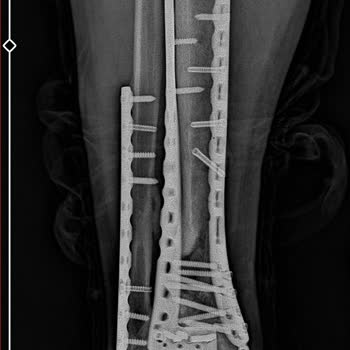

Kocaeli Derince’de, Sağlık Bakanlığı’na bağlı hastanede 2024 yılında engellilik raporu için başvurdum. Dört yıl önce geçirdiğim iş kazasında sağ bacak tibia ve fibulada çok parçalı kırık oluştu ve o günden beri baston kullanmadan yürüyemiyorum. Buna rağmen engel oranım sadece yüzde 24 olarak verildi.

Kocaeli Gölcük Necati Çelik Devlet Hastanesi’nde 2024 yılında erişkin engellilik oranı raporu için değerlendirmeye girdim. Sağ bacağımda 4 yıl önce geçirdiğim iş kazası sonucu fibula ve tibia kemiklerimde çok parçalı kırık oluştu, bu kaza sonrası sakat kaldım ve bastonsuz yürüyemiyorum. Buna rağmen tarafıma yalnızca yüzde 24 engellilik oranı verildi, en az yüzde 45 verilmesi gerektiğini düşünüyorum.